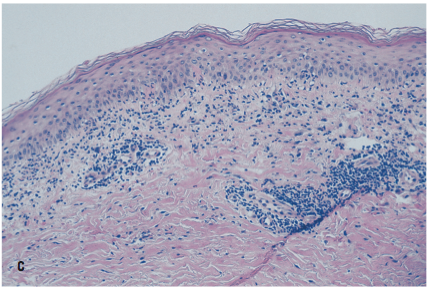

Microscopic examination of material from a lesion showed spongiosis (edema surrounding the individual keratinocytes in the epidermis) and a bandlike, chronic inflammatory infiltrate at the dermal-epidermal junction (C). In addition, apoptotic, or dying, keratinocytes were noted at the basal layer of the epidermis.